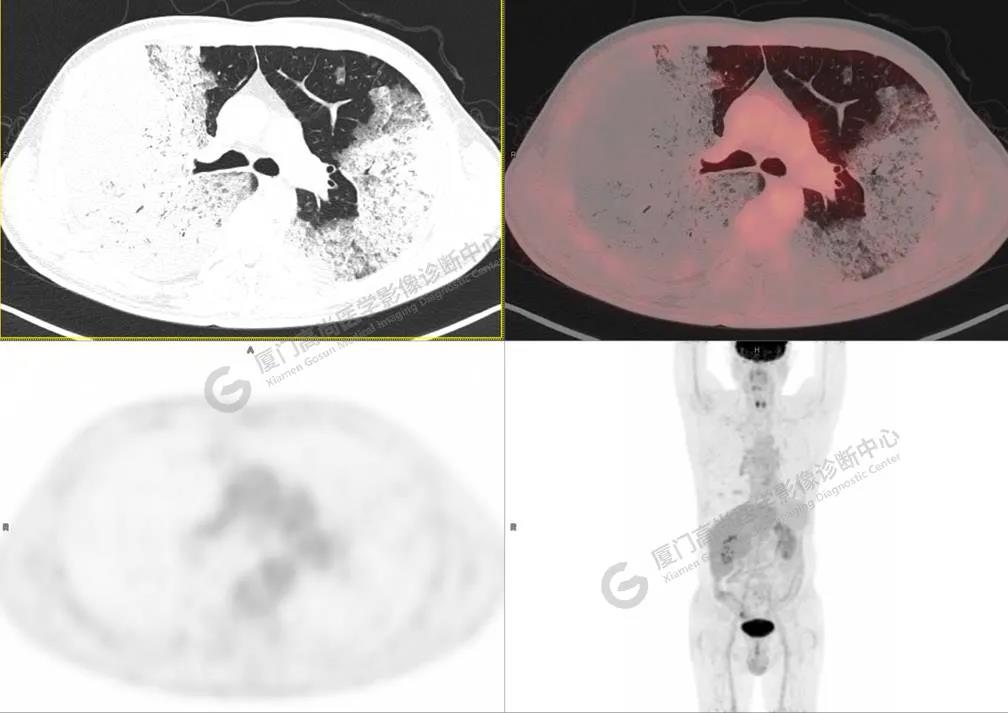

圖2

PET/CT所見:雙肺大片實(shí)變影及磨玻璃影,部分呈地圖樣改變,累及右肺尖,部分放射性攝取輕微增高,SUVmax 1.77,其內(nèi)見多發(fā)支氣管充氣征象。

影像診斷: 雙肺大片實(shí)變影及磨玻璃影,大部分代謝不高,局部代謝輕微增高,考慮肺泡蛋白沉積癥,建議病理學(xué)檢查或肺泡灌洗物檢查。

影像學(xué)表現(xiàn):HRCT上雙肺斑片影,以肺門為中心呈蝶翼狀對稱分布;病變可隨機(jī)分布在中央?yún)^(qū)、周圍區(qū)或全肺葉,病灶與正常分組織分界清楚,呈典型“地圖樣”改變;有支氣管充氣征,但表現(xiàn)為充氣支氣管細(xì)小且數(shù)量及分布稀少;“碎石路”征由彌漫性磨玻璃影及內(nèi)部網(wǎng)格樣小葉間隔增厚組成(鋪路石樣表現(xiàn))。無空洞、蜂窩狀改變、淋巴結(jié)腫大、胸腔積液及明顯實(shí)變等。肺內(nèi)病灶累及范圍、磨玻璃密度高低與PAP患者的病情嚴(yán)重程度相關(guān),嚴(yán)重者病灶累及全肺,同時出現(xiàn)肺內(nèi)大片實(shí)變,并見充氣支氣管征象。PAP影像學(xué)表現(xiàn)程度與臨床癥狀、體征嚴(yán)重程度不成比例,表現(xiàn)為影像改變重,臨床癥狀輕。